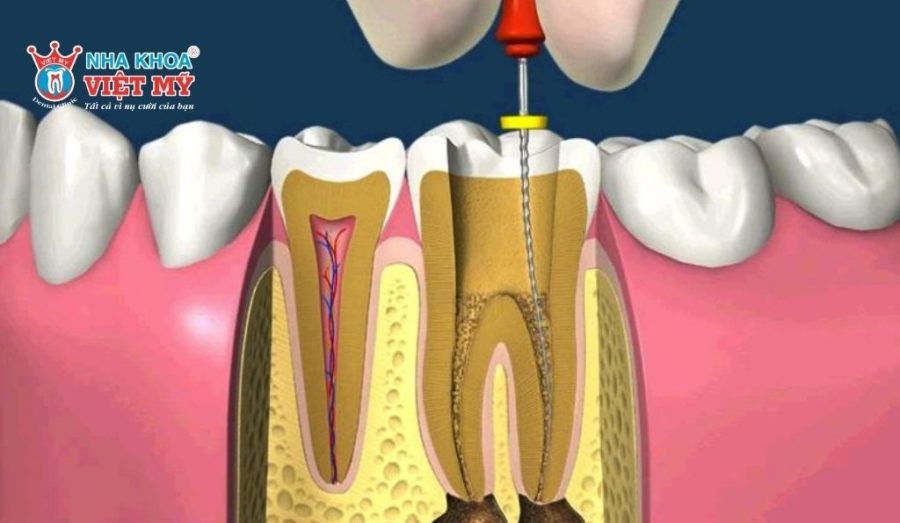

Lấy tủy răng là một phương pháp nha khoa nhằm loại bỏ hoàn toàn tủy răng bị tổn thương hoặc viêm nhiễm do sâu răng, gãy răng, chấn thương … Sau khi làm sạch, bác sĩ sẽ trám bít lại các ống tủy bằng vật liệu chuyên dụng. Mục đích cuối cùng của việc lấy tủy là giải quyết triệt để nguồn nhiễm trùng, chấm dứt cơn đau và bảo tồn chiếc răng thật khỏi nguy cơ phải nhổ bỏ. Bạn cần phải thực hiện thủ thuật này ngay khi xuất hiện các dấu hiệu nghiêm trọng sau:

- Trám bít ống tủy chưa kín hoàn toàn: Do đặc điểm phức tạp của hệ thống ống tủy, vật liệu hoặc điều kiện lâm sàng, việc trám bít có thể chưa đạt độ kín tuyệt đối. Khi đó, vi khuẩn từ môi trường miệng có thể xâm nhập ngược qua ống tủy, gây nhiễm trùng thứ phát.

- Tổn thương cấu trúc răng: Trong một số trường hợp ống tủy cong hoặc thành mỏng, có thể xảy ra thủng sàn tủy hoặc chóp tủy trong quá trình điều trị. Những tổn thương này có thể dẫn đến viêm cấp tính ở mô quanh chóp và cần được chẩn đoán, xử trí phù hợp.

- Cấu trúc ống tủy phức tạp: Một số răng có ống tủy bị cong, hẹp hoặc có nhiều ống tủy phụ khó tiếp cận. Điều này khiến việc làm sạch và trám bít trở nên khó khăn, dễ dẫn đến sót tủy hoặc không trám bít được hết.